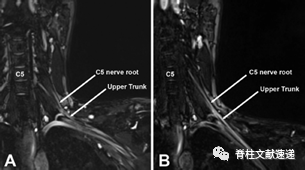

图注:依次用10,20,30磅在左臂上牵引,测量了脊髓轴与C5神经根之间的夹角(a)以及C5神经根与臂丛上干之间的夹角(b)。

肩关节牵拉常用于下颈椎更好的透视成像与手术暴露,但C5神经根的牵引被认为是C5麻痹的潜在原因;

C5神经根与脊柱轴(a)之间的夹角保持在均值3-4°内,与牵引重量的增加没有相关性;C5根与臂丛上干的夹角(b)随体重的增加而增加,差异有统计学意义;

上肢受力与C5根-上干角度的增加有明显的线性关系;

麻醉患者,肩关节牵引可能导致C5神经根的张力增加,导致神经根损伤和麻痹。